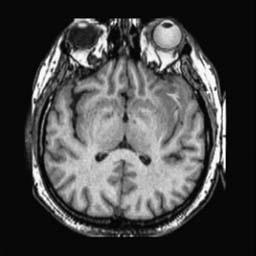

To demonstrate the effectiveness and efficiency of the proposed image fusion method , we conduct a set of comparative experiments on three image datasets. The first is composed by 8 pairs of multi-modal medical images and the second one contains 15 pairs of multi-focus gray or color natural images. These two datasets are often used in many related papers and some examples are shown in Figure 3(a) and Figure 3(b). The third one is a new multi-focus cervical cell image dataset collected by ourselves, which consists of 15 groups of color images and each group contains a series of multi-focus cervix cell images with size of or , etc. Some source examples are shown in Figure 3(c). Our source code implemented in C++ along with the new multi-focus cervical cell image dataset is available online.

We first evaluate the performance of the proposed method under varying total number of octaves and number of layers sampled per octave. The fused images of a pair of multi-modal medical images with different and are shown in Figure 4. In this example, on the one hand, when only 1 or 2 octaves are involved in constructing the DoG pyramid, the fused images fail to keep the integrity information of large size objects (e.g. eyeballs), while by increasing the value of , the integrity information of eyeballs is preserved. On the other hand, although not as significant as the increase of octave numbers , the fused image can contain more details by the increase of layer numbers . The corresponding objective quality metrics are shown in Figure 5. As shown in Figure 5(a), most of the metric values are improved as the number of octaves increases with the fixed layer numbers 3 in the global tendency and each of them tends to be stable when the number of octaves is 5. To get a relatively good quality from Figure 5(b), we can notice that some of the metric values can get a good performance when the number of layers is 3, such as the MI, SSIM, QI and VIF, though there are only a little change of all the metric values by increasing the number of layers with the fixed octave numbers 5. Because it will result in more computation burden with the increase of the value and , and for different kinds of source images, there are different performance with the diverse parameter settings. To get a trade-off between them in our experiments, we set for the multi-modal dataset, for the natural datasets and for the multi-focus cell dataset, respectively.

Figure 6 shows the fused images obtained by different methods with the multi-modal source images shown in Figure 3(a). As shown in these figures, the proposed method can produce images which preserve the complementary information of different source images well. Moreover, due to the scale-invariant structure saliency selection, our method can keep the integrity information of large size objects and the visual details simultaneously. Although the fused image generated by other methods can also capture the details to some extent, all of them fail to keep the integrity information of large size objects such as the eyeballs. Furthermore, from Figure 6(k)-6(t), the DTCWT, GFF, IM and NSCT methods may decrease the brightness and contrast while the proposed method can preserve these features and details without producing visible artifacts and brightness distortions.